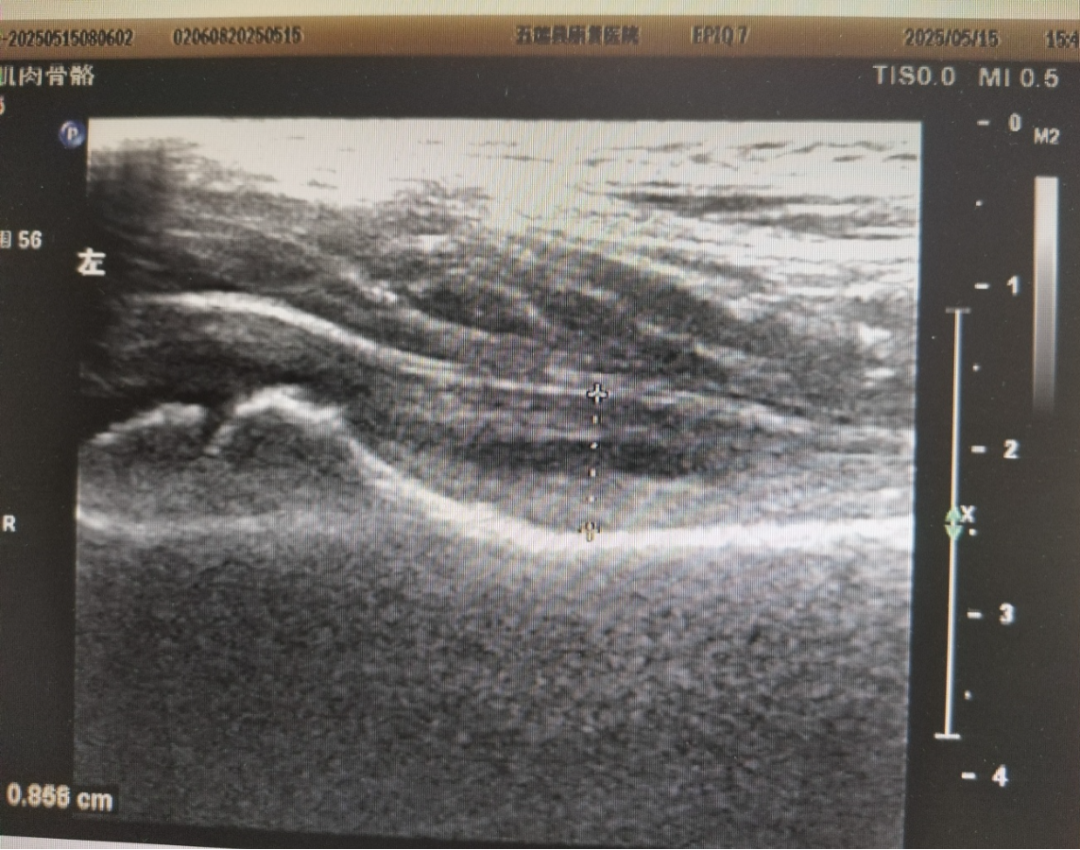

6岁的小星(化名)最近几天总跟妈妈喊腿疼,起初妈妈以为孩子是在撒娇逃避上学。直到某天清晨,小星起床后右腿突然无法站立行走,右侧大腿根部内侧、前侧及腹股沟区疼痛明显,家长立即带他就医。临床医师为明确诊断申请髋关节肌骨彩超检查,结果显示:患儿右大腿根部前侧及内侧区肌肉结构正常,纹理清晰,未见明显肿胀、断裂或血肿形成,但髋关节腔内及股骨颈前隐窝可见明显积液,关节囊滑膜增厚,最终确诊为髋关节暂时性滑膜炎,所幸得以及时治疗。

1. 超声检查(首选)

典型表现:

(1)髋关节前隐窝积液(股骨颈与关节囊间无回声区,厚度>2mm)。

(2)滑膜轻度增厚,但无显著血流信号(与感染性关节炎鉴别)。

优势:无辐射、动态观察、可床边操作。